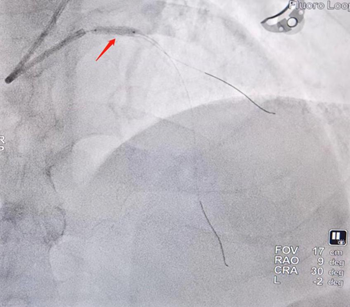

冠脉造影提示左主干至前降支近段重度狭窄,且全程可见明显钙化影。洪浪、尹秋林团队应用冠脉腔内影像学技术-OCT对该血管进行了进一步的评估,结果显示:左主干至前降支近段全程可见环形钙化,最严重处位于左主干末端,此种情况极易造成支架膨胀不全。团队先使用冠脉内旋磨术对冠脉钙化病变进行旋磨,然后使用冲击波球囊对钙化病变进行处理。结果显示严重钙化处出现钙化断裂,提示支架植入后可以获得满意的支架膨胀效果。

左主干-前降支造影:严重钙化狭窄病变